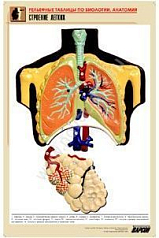

14. Строение легких;

Изделие соответствует Перечню средств обучения и воспитания, утвержденному Приказом Минобрнауки России N 804 (подраздел «Демонстрационные учебно-наглядные пособия для профильного медико-биологического класса»).